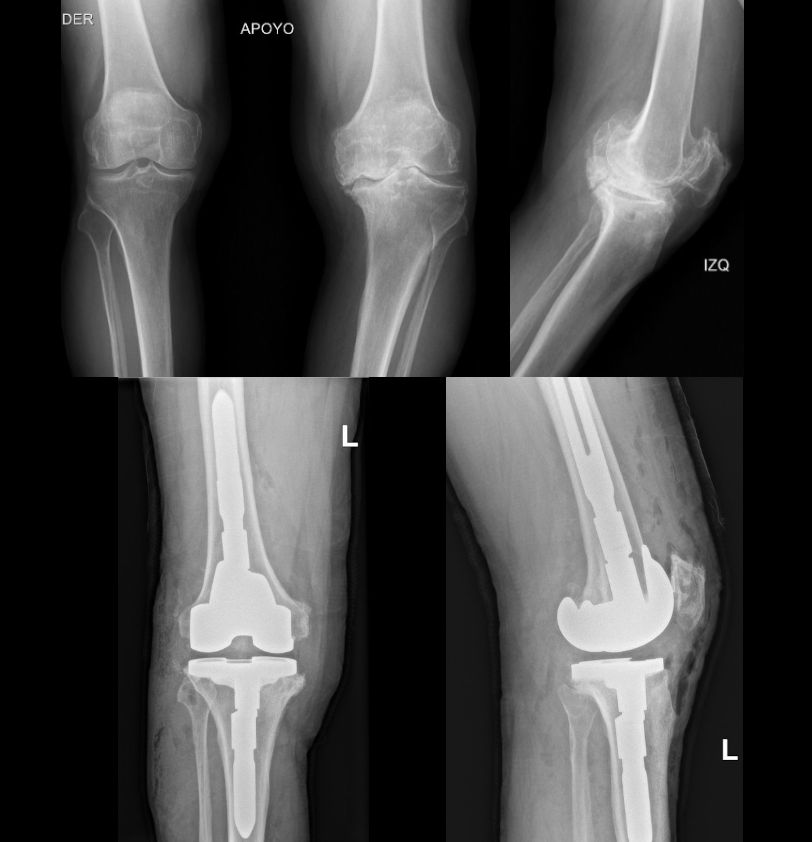

• Artrosis de rodilla

• Osteoartritis

• Deformidades en rodilla

Artroplastia de la rodilla Sin especificar